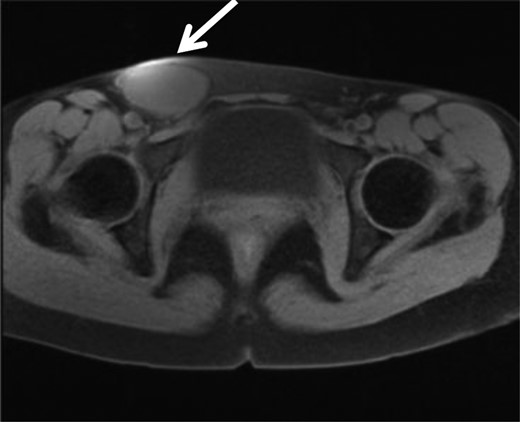

A 35-year-old woman was referred to our hospital for a painful right groin tumor which grew in size which was not related to her menstrual cycle. With the diagnosis of inguinal endometriosis, she had been treated with two cycles of low-dose birth-control pills, and five cycles of genogest previously, but the groin was increased in size to 5-cm with pain. In her past medical history, no history of gynecologic problems and specifically no dysmenorrhea nor dyspareunia were recorded. In the right groin, there was a 5-cm bulge which was detected as a homogeneous hypoechoic subcutaneous tumor and measured 53 × 29 mm by ultrasonography (Fig. 1). Her serum cancer antigen-125 was elevated to 95.4 U/ml (range <35 U/ml) before starting hormone therapy, and down to 40 U/ml when she came to our hospital even though the tumor size was unchanged. Magnetic resonance imaging (MRI) revealed a 6-cm unilocular tumor with internal high intensity in T1WI image which suggested internal bleeding (Fig. 2). We diagnosed the right inguinal tumor as a Nuck cyst. An inguinal approach was selected and after opening the skin and subcutaneous fat, a dark red tumor was founded which protruded from the femoral ring, in spite of our initial impression that the tumor was located along the round ligament (Fig. 3). After careful dissection, the tumor turned to be a unilocular cyst containing serous fluid, which was connected with the peritoneum through a string structure at the femoral ring, which was not connected with the abdominal cavity. The cyst was excised and the string structure was resected at the femoral ring. We inserted a plug into the extended femoral ring, and confirmed no other hernia. Her postoperative course was uneventful, and she was discharged on the first postoperative day. The histopathologic examination showed that mesothelial cells lined the wall of the cyst with degeneration, inflammation, hemorrhage, formation of hyperplastic collagen fiber and hemosiderosis without malignancy (Fig. 4). The immunohistochemistry [Calretinin(+)] confirmed the mesothelial origin of the cyst-lining cells and [CD10(+), ER(+), PgR(+)] suggested the endometrial origin of a few stromal tissue composing the cystic wall. As of 10 months after the operation, no recurrence of hernia or cyst has been encountered.

MRI showed a high intensity tumor in T1WI which suggest bleeding in the tumor, in the right inguinal region.